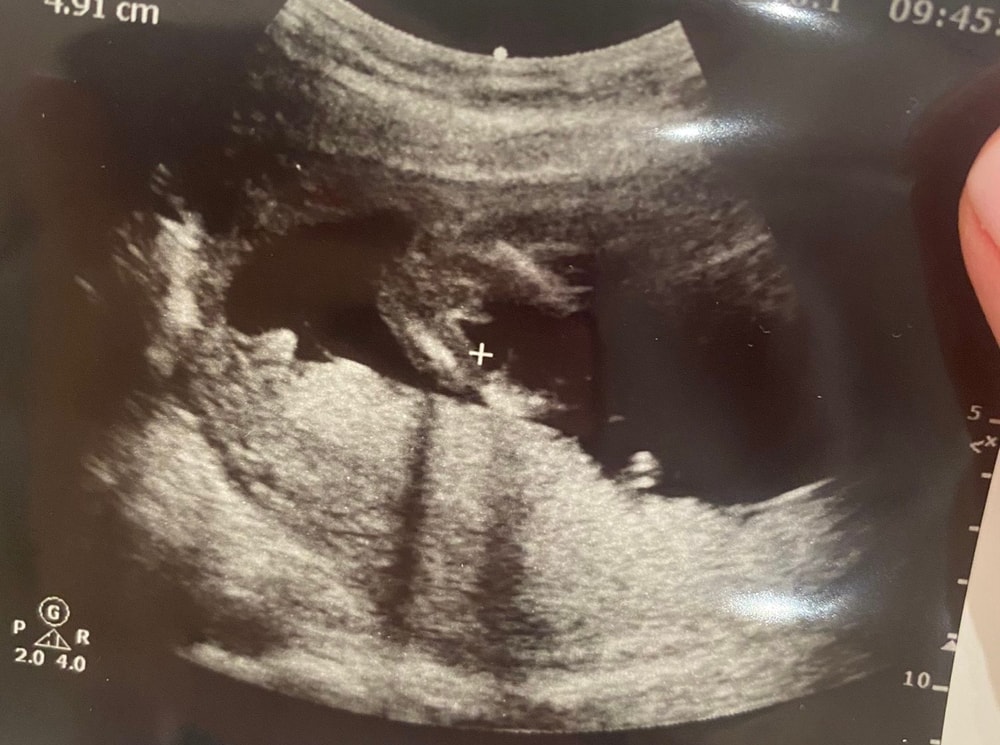

Пол ребенка

Пацан же)

Вы видели когда-нибудь таких девочек? 😅

Мальчик 100%) все отчётливо видно 😅

У меня есть похожее фото, там пуповина. Но между ножек видно три полосочки, у вас такого не вижу. На узи что сказали?

Узнаем пол малыша Пол по узи